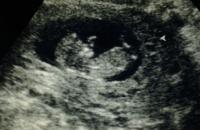

10 kérdés és válasz a terhesség alatti szexről

A kétcsíkos teszt után sok minden megfordul az ember fejében. Kinek előbb, kinek később valószínűleg ez is eszébe jut: mi lesz most a szexszel? Mert hát szeretkezés nélkül lehet ugyan élni kilenc hónapig, de ha nem muszáj,... »